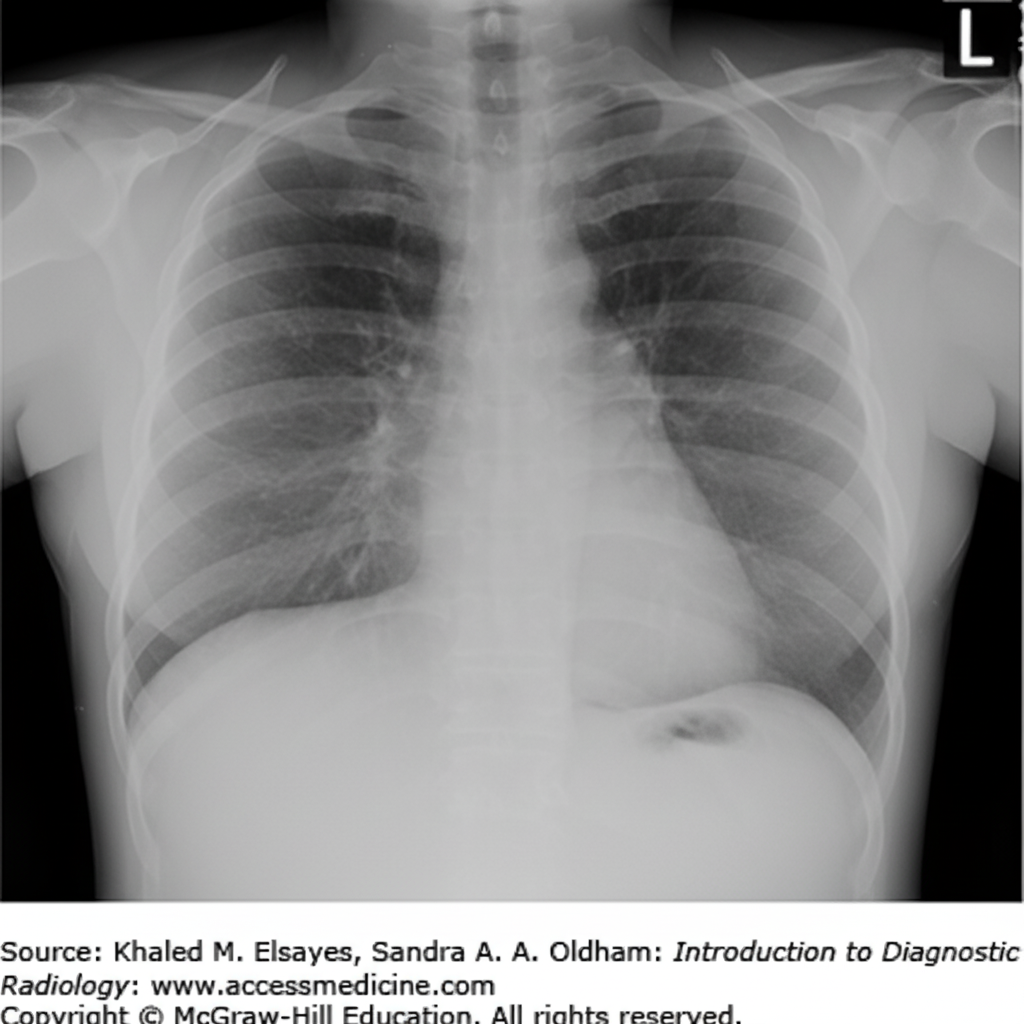

A 41-year-old man presents with severe shortness of breath. He reports a 25-lb weight loss over the last 2 months and occasional vomiting after meals. His vital signs are: pulse 110 bpm, temperature 98 F, respirations 24/min, and blood pressure 110/70 mm Hg. Physical examination reveals dullness to percussion on the left posterior chest with decreased breath sounds. Egophony is heard over the left upper lung field posteriorly. A PPD test is 15 mm. A chest X-ray is shown. What is the most likely diagnosis?

Explanation: ***Pleural effusion*** - The classic triad of **dullness to percussion**, **decreased breath sounds**, and **egophony** over the left upper lung field strongly indicates pleural effusion. - The **positive PPD (15 mm)** combined with **weight loss** and **systemic symptoms** suggests **tuberculous pleural effusion** as the underlying cause. *Aspiration pneumonia* - Typically presents with **bronchial breath sounds** and **consolidation** rather than the dullness and decreased breath sounds seen here. - Usually occurs in patients with **risk factors** like altered consciousness, dysphagia, or neurological impairment, which are not mentioned. *Community-acquired pneumonia* - Would present with **fever**, **productive cough**, and **bronchial breathing** with consolidation on examination. - Physical findings would include **increased vocal fremitus** and **bronchophony**, not the decreased breath sounds and egophony pattern seen. *Left lung atelectasis* - Would cause **tracheal shift** and **mediastinal shift** toward the affected side due to volume loss. - Typically presents with **decreased chest expansion** on the affected side and different breath sound patterns than described.